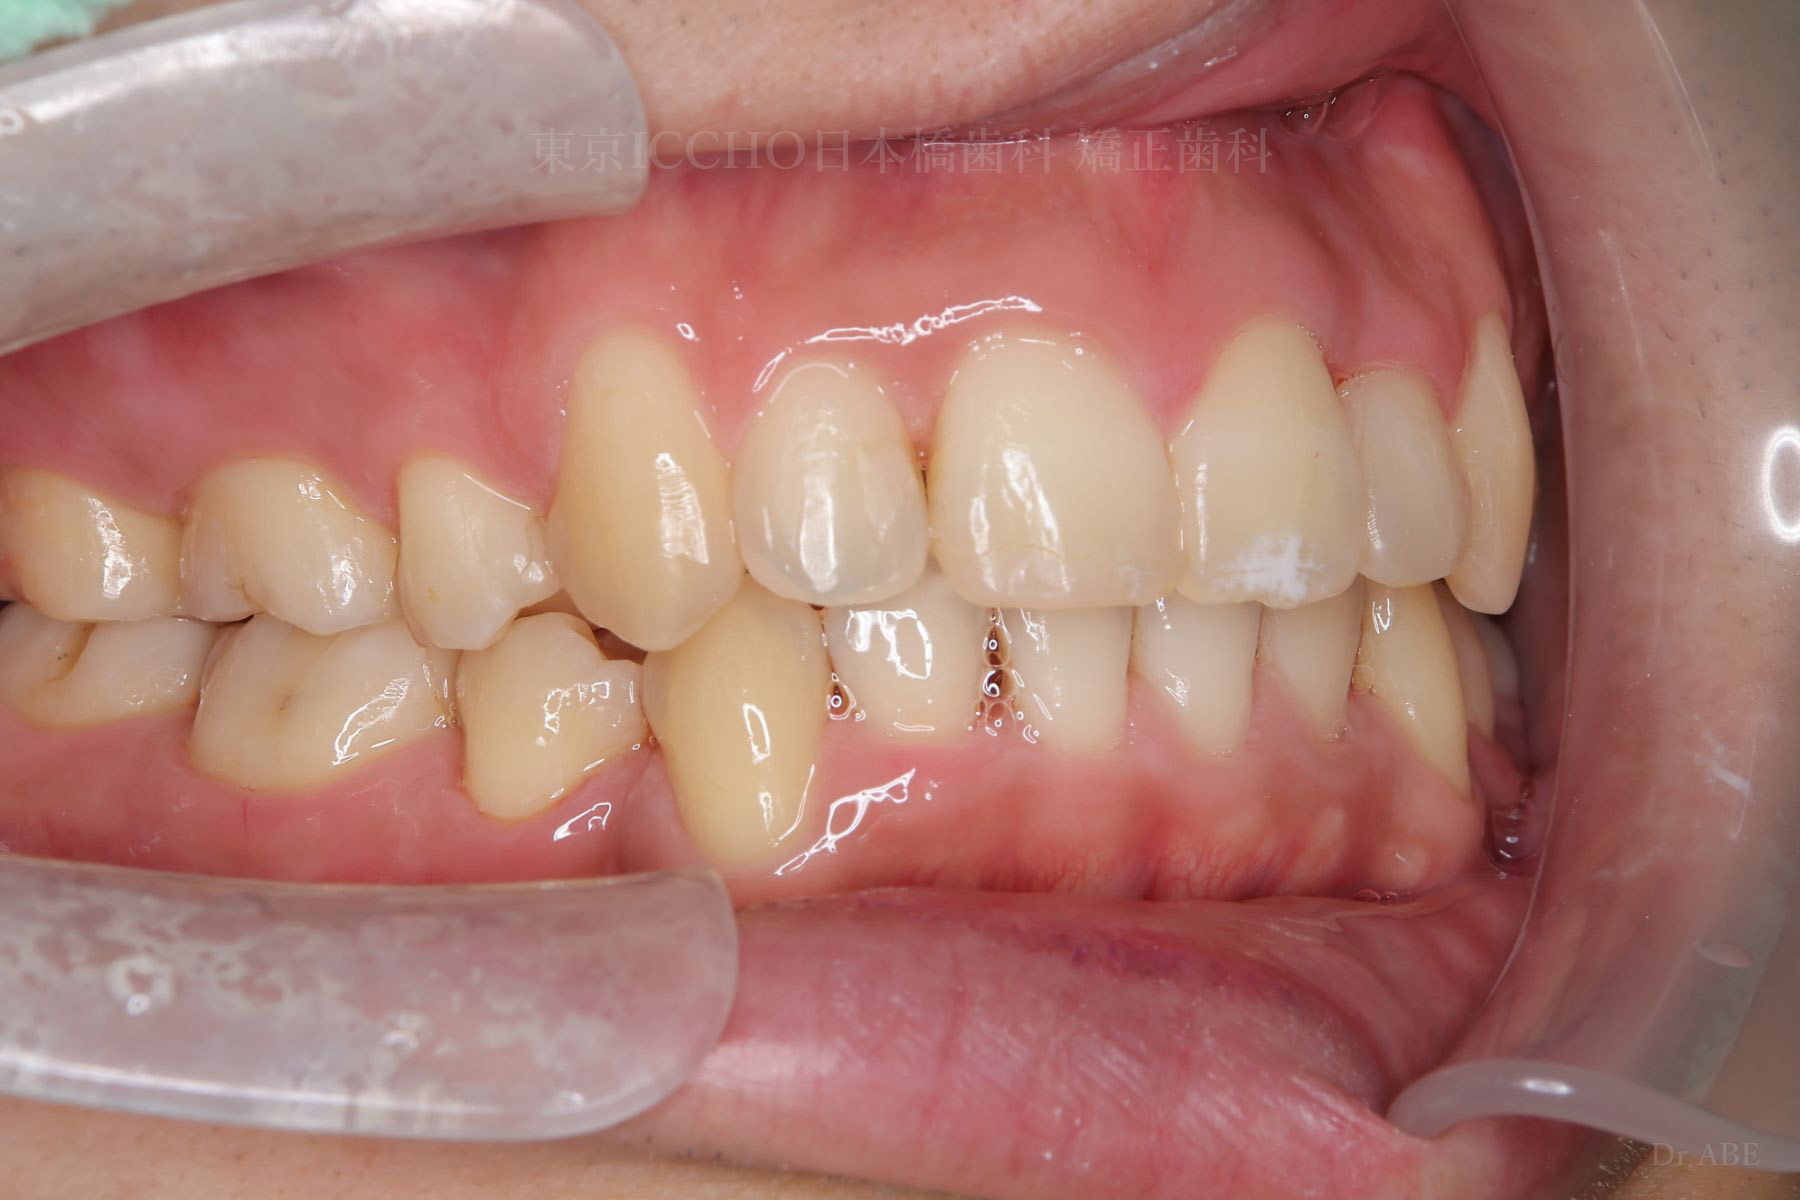

治療後

治療内容 かみ合わせの不正と顎が小さいため、上下左右第一小臼歯4本の抜歯を行い前歯を後ろへ下げた。

また、前歯が噛まない状態のため、かみ合わせを少し下げて噛むように誘導し、全体的にかみ合わせとして機能的な矯正治療を行った。